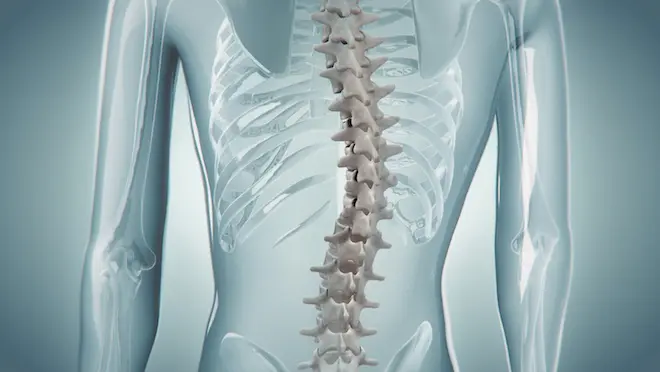

À 15 ans, Julia souffre de la malformation orthopédique la plus fréquente chez l'adolescent : la scoliose. Depuis la puberté, sa colonne vertébrale ne cesse de se tordre. Elle est aujourd'hui tellement déformée qu'elle fait souffrir la jeune fille, et qu'elle menace, à terme, de l'handicaper lourdement. Julia n'a plus le choix. Soutenue par Marie et Olivier, ses parents, elle a dû se résoudre à la chirurgie.

Une chirurgie impressionnante et extrêmement délicate, puisqu'elle consiste à fixer des tiges en titane dans sa colonne vertébrale, à quelques millimètres à peine de sa moelle épinière. Un petit écart de trajectoire et c'est toute la motricité de la jeune fille qui est menacée.

- Une plongée dans l'anatomie

Pour bien comprendre cette chirurgie complexe, des animations 3D montrent ce que la caméra ne peut pas saisir.